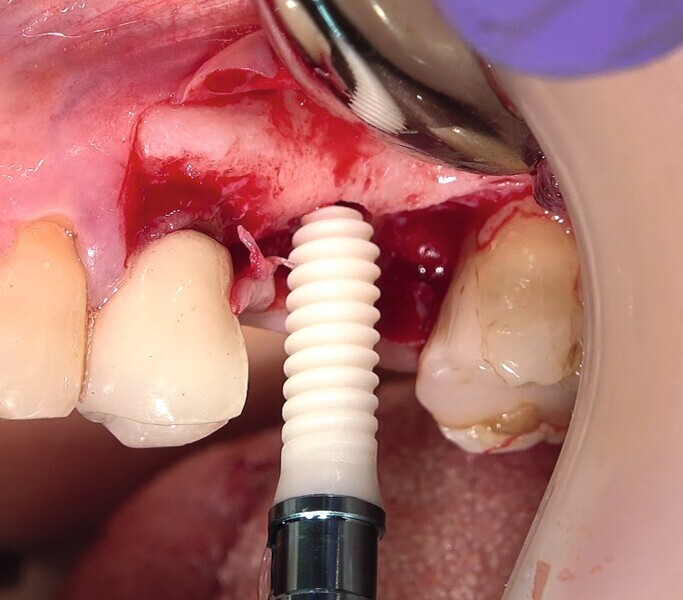

Fig. 27 : Pose de l’un des implants deux pièces en céramique au niveau tissulaire.

Fig. 28 : Pose de l’un des implants deux pièces en céramique au niveau tissulaire.

La crête alvéolaire au niveau du site de la molaire inférieure était trop étroite pour permettre la pose prédictible d’un implant sans une augmentation osseuse préalable. Des implants deux pièces en zircone ont été mis en place, simultanément à une augmentation osseuse latérale, au moyen d’une allogreffe et d’une membrane de collagène résorbable (Figs. 25–34).